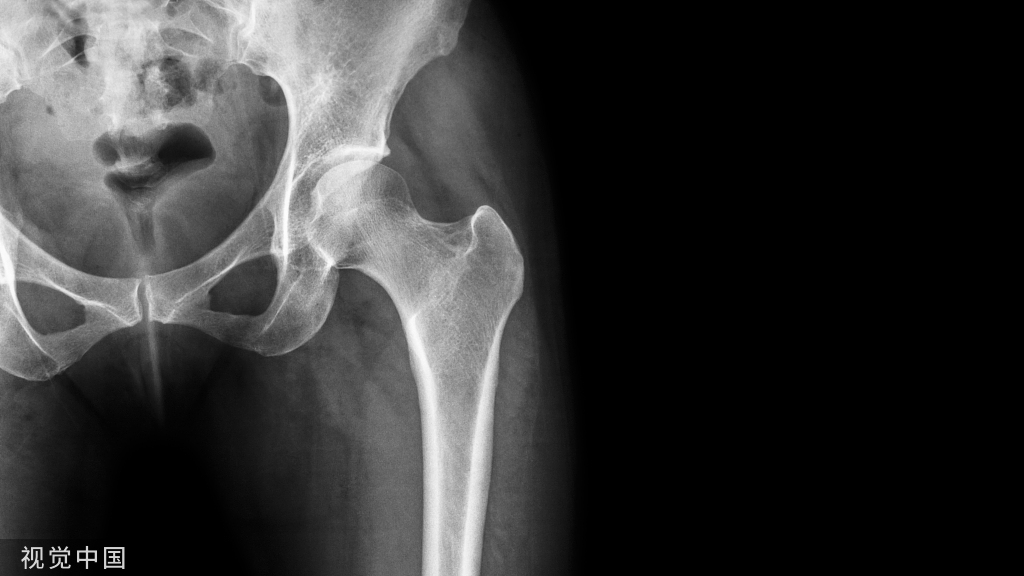

1)股骨近端(股骨头,颈,转子部位)

- <65岁,内固定;>65岁,关节置换。

- 患者全身情况稳定,应早期内固定。

- 内固定方式很多,如DHS,pfna等。